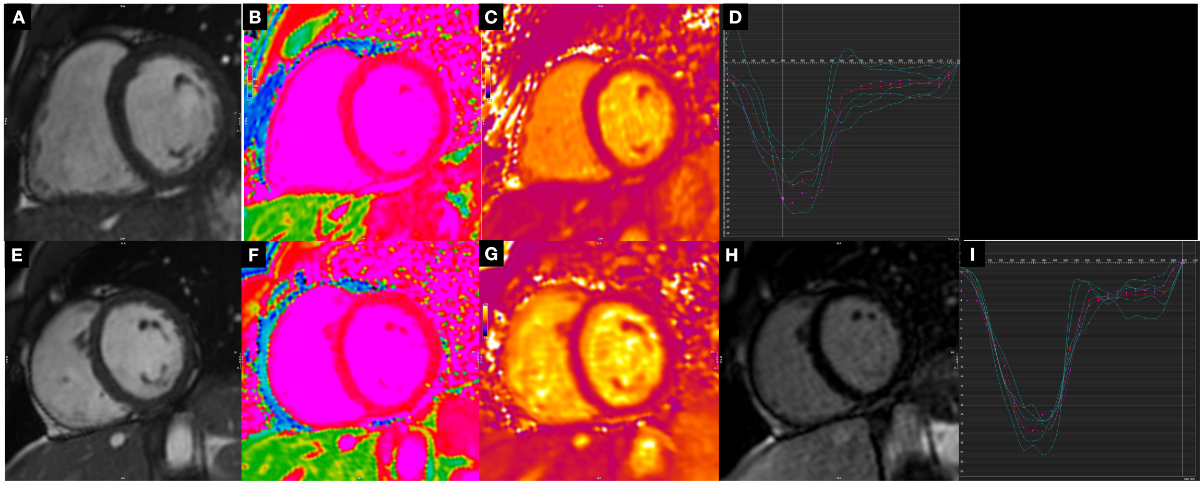

LGE imaging did not reveal any abnormalities in myocardial tissue characterisation indicating myocardial damage. None of the athletes met the current Lake Louise criteria for acute myocarditis [15]. To account for the potential confounding effects of age, weight, height, and BMI, we also performed analysis of covariance (ANCOVA). After this adjustment, no differences retained statistical significance. However, the inclusion of control variables in the ANCOVA model was constrained by the sample size; our small sample size may have limited statistical power, and the introduction of multiple control variables warrants careful consideration given the potential complications in interpretation. The full details of the cardiac magnetic resonance findings are presented in table 2; figure 2 shows exemplary cardiac magnetic resonance images and strain analyses of a control (A–D) and an athlete (E–I).

Figure 2Panels A–D show example images from a participant in the control group: (A) still frame of a medial short-axis cine image, (B) the corresponding T1 map, (C) the related T2 map, and (D) the associated strain analysis with image A. Panels E–I show examples from an athlete: (E) still frame of a medial short axis cine image, (F) the corresponding T1 map, (G) the related T2 map, (H) the late gadolinium enhancement image, and (I) the circumferential strain curve associated with image E.